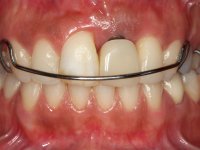

A paciente apresenta um desvio da linha média superior de 6 mm para a esquerda. Resultado da ausência do incisivo central superior esquerdo, os dentes adjacentes inclinaram mesialmente para esta zona, limitando o espaço disponível para a reabilitação prostodontica. Existe uma significativa desarmonia dentária negativa no arco maxilar como resultado da ausência do 21, ausência do primeiro pre-molar com um espaço residual, significativa redução coronária do segundo pre-molar direito, migração dos dentes posteriores para os espaços não preenchidos e uma mesialização molar superior esquerda e direita com uma relação molar em Classe II. Ambos os caninos esquerdo e direito mostram uma relação Classe II na posição de inter-cuspidação máxima. A paciente apresenta uma linha de sorriso média, um biótipo gengival médio grosso, apresenta uma correcta higiene oral sem doença periodontal. Não apresenta hábitos para –funcionais. O exame radiográfico mostra uma significativa inclinação dos eixos dos dentes 11 e 22 com espaço entre a porção apical das raízes. A análise cefalométrica foi feita com o intuito de explorar a hipótese de conseguir arranjar espaço para a colocação de um implante e de uma coroa no local do dente 21. Finalmente a morfologia do osso residual presente na região anterior da maxila foi avaliado com uma TAC, revelando uma perda das dimensões da parede óssea vestibular.

Tendo em conta a relação de Classe II molar e canina, o plano de tratamento contemplou a seguinte abordagem multidisciplinar:

2) Tratamento ortodôntico com o objectivo de criar espaço entre as raízes e as coroas dos dentes 11 e 22,